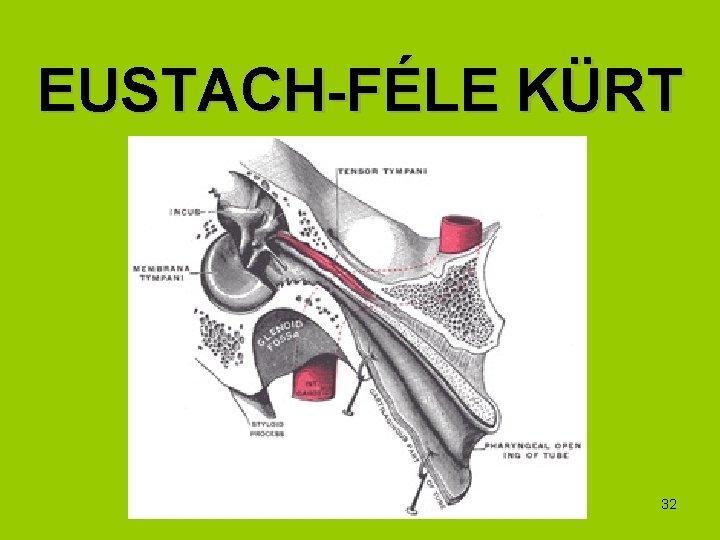

EUSTACH-FÉLE KÜRT 32